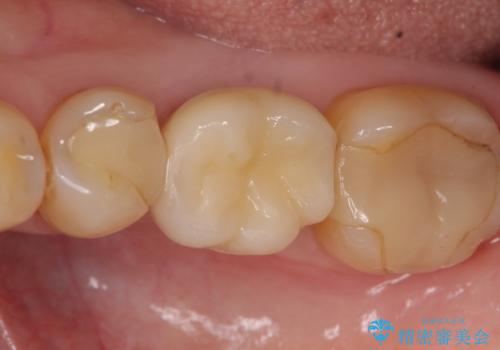

ストローマンについて

当院では主にストローマンという種類のインプラントを治療に用いています。

ストローマンは世界的にもNo1のシェアを誇り、骨との適合にも優れたインプラントです。

オールセラミッククラウンについて

今回用いたオールセラミッククラウンはジルコニアフレームという白い素材の上にセラミックを盛っているため、審美性が非常に高いのが特徴です。

また、ジルコニアは人工ダイヤモンドの材料にも使われているほど高い強度を持っており、そのためオールセラミッククラウンは審美性だけでなく、奥歯やブリッジの補綴も可能とするクラウンです。